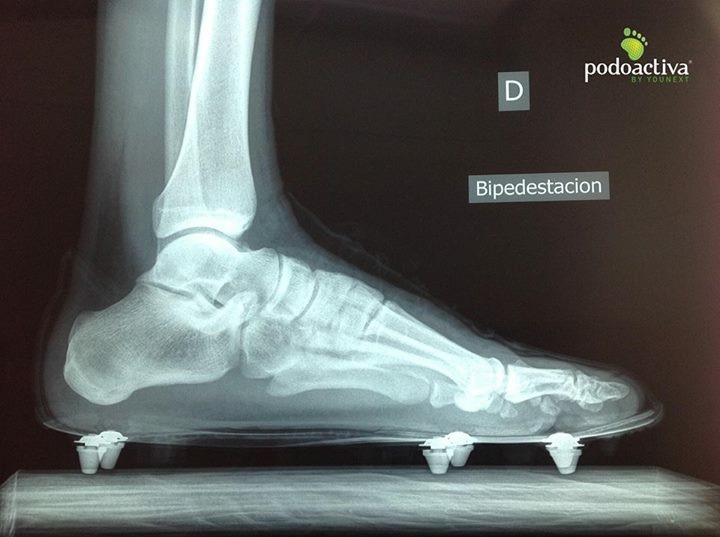

Si después de comenzar a usar una bota comienza a aparecer un dolor selectivo en una articulación metatarsal, debemos de dejar de usar la bota cuanto antes y analizar la posición del taco. Una prueba válida para esto es hacer una radiografía lateral del pie con la bota puesta en la que podremos valorar si el problema puede venir por la posición del taco.